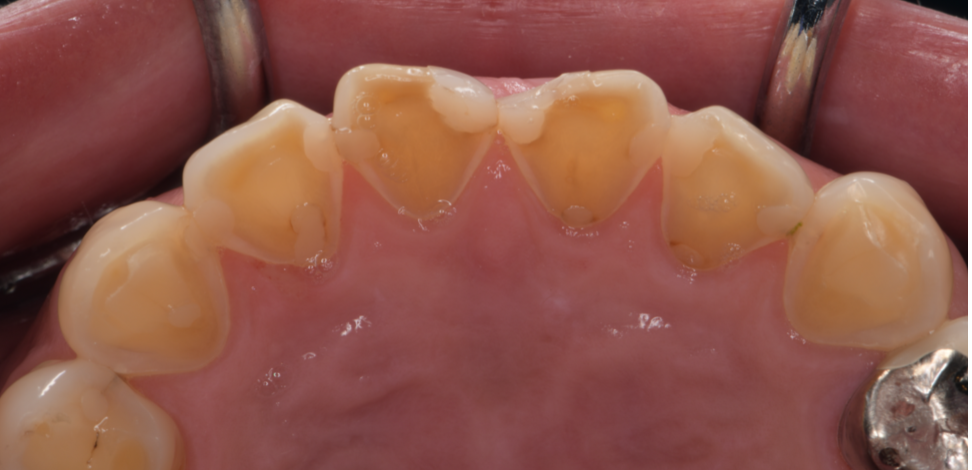

前歯の見た目が気になり来院されたケース

前歯のすき間や欠け、変色が気になっていませんか?「できるだけ歯を削りたくない」「自然な仕上がりにしたい」「その日のうちにきれいにしたい」――そんな方に選ばれている治療がダイレクトボンディングです。

今回は、前歯の見た目をダイレクトボ…